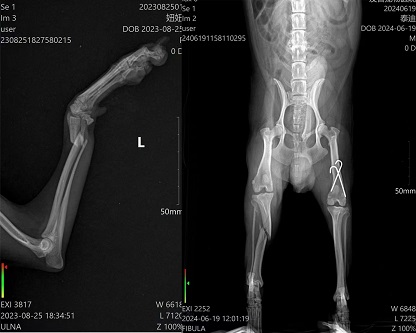

11月6日零基础骨科班现报名人数已满,感谢学员们的信任与选择。已超出本期报名名额的学员安排在本年度12月底一期。本班课程为5天,学员从骨解剖、麻醉、手术通路、骨折骨板、缝合、术后X片及用药全部为实体操作。无围观、无PPT,全天侯手把手教学操作,学后确保独立完成骨科手术。